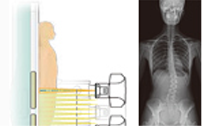

持续呈现高质量图像

Neo-Vision使用了多种检查方案独立设置的采集模式。可定制化的采集方案可以使采集时的X线曝光曲线及图像后处理更加的精准,图像清晰度更高。

Neo-Vision产品使用了轻便,可移动的无线动态平板探测器。可以轻松的进行透视及普通X射线摄影的切换。

双屏双显的显示模式有效的把动态图像及静态图像分开,既可以完成准确的定位及观察,同时可以进行图像 的分析及诊断。大大提高了使用者操作的便利性及诊断的准确性。